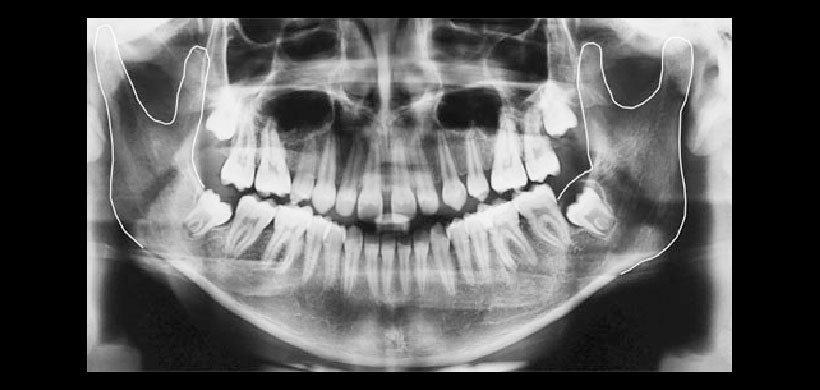

Radiografía panorámica: nos permiten determinar en las radiografías panorámicas la simetría entre planos comparando ambos lados de la mandíbula en un mismo paciente, entregando una visión generalizada de la articulación temporomandibular. Su desventaja radica en la distorsión geométrica.

Figura 2: Radiografía panorámica, es el examen más solicitado y en el cual se debe realizar la evaluación preliminar de los cóndilos mandibulares.